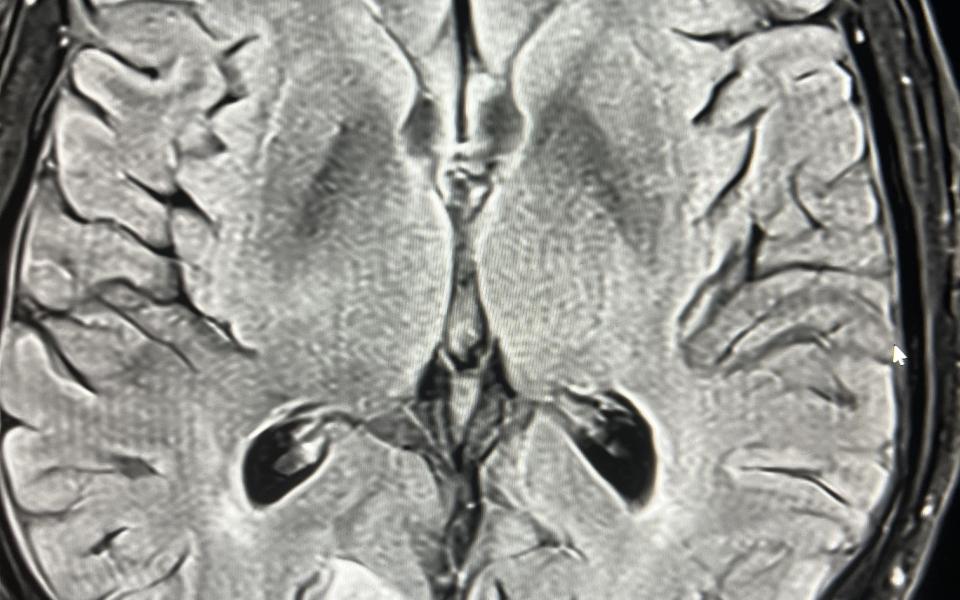

A 77 male presented with a 10 history of visual symptoms following heavy exertion. He described it as an afterimage on his left temporal field eg he would see a person walking past and then see them